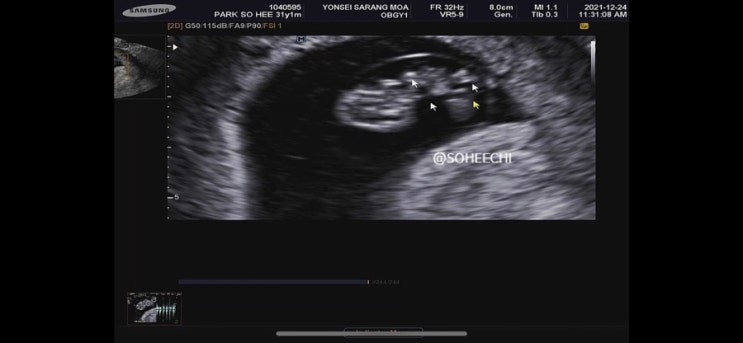

ㅁ 7/20 토리 출산 ㅁ 38주 1일차 2.99kg ㅁ 연세사랑모아여성병원에서 제왕절개 제왕절개 3일차 병원에서 ...